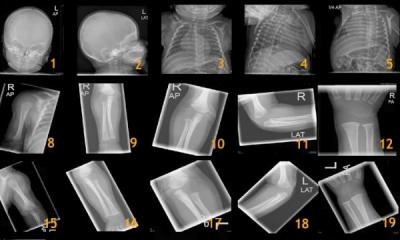

International Day of Radiology 2015 focuses on children

This year, the worldwide International Day of Radiology (IDoR) on 8 November is dedicated to paediatric radiology. Professor Erich Sorantin, Head of Paediatric Radiology at the University Hospital Graz (Austria) and IDoR coordinator for Austria is particularly pleased: “Only very few countries recognize paediatric radiology as a radiological sub-speciality. Now we have the opportunity to highlight the crucial role of imaging in the detection, diagnosis and management of paediatric diseases.”